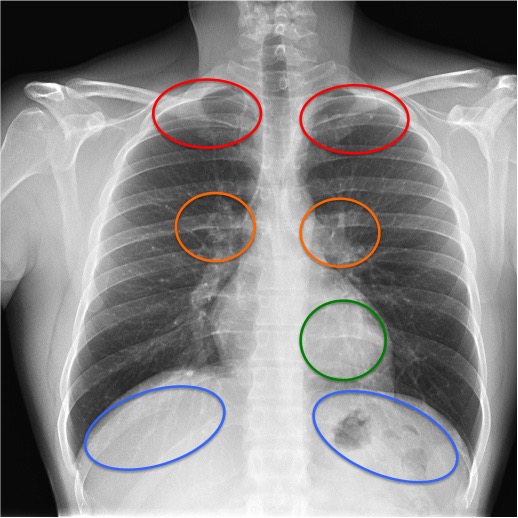

CASO: Disnea. Paciente con insuficiencia cardiaca.

Hallazgos:

- Cardiomegalia.

- Signo del 3º mogul y doble contorno por crecimiento de la aurícula izquierda.

- Bronquio izquierdo rectificado por crecimiento de la aurícula izquierda (signo de la bailarina).

- En la placa lateral, además se observa elongación aórtica.

- Parénquimas pulmonares sin hallazgos.

Signo del doble contorno: La AI aumentada de tamaño produce un segundo contorno que normalmente no debería figurar (flecha naranja contínua).

Flecha amarilla: cayado aórtico.

Flecha verde: arteria pulmonar.

Flecha azul: ventrículo izquierdo.

Signo del tercer mogul: se refiere a la lobulación anormal del contorno mediastínico izquierdo entre la arteria pulmonar y el ventrículo izquierdo. Pueden producir esta lobulación lesiones cardíacas y pericárdicas (orejuela izquierda aumentada, aneurisma ventricular o de la arteria coronaria, quiste o masa pericárdicos, etc) y también algunos tumores mediastínicos, como timomas. En la imagen, el signo corresponde al crecimiento de la orejuela izquierda (flecha roja). La palabra “mogul” es un término utilizado por los esquiadores para describir un acúmulo mamilar de nieve compacta en una ladera montañosa. El primer mogul corresponde al cayado aórtico (flecha amarilla); el segundo, a la prominencia de la arteria pulmonar (flecha verde); y el cuarto, al contorno del ventrículo izquierdo (flecha azul).

Signo del doble contorno: indicativo de crecimiento de la aurícula izquierda en la radiografía posteroanterior de tórax. La aurícula izquierda no forma parte normalmente del contorno cardiaco derecho en esta proyección; sin embargo, cuando aumenta de tamaño, produce un segundo contorno (flecha narana contínua), además del de la aurícula derecha (flecha naranja discontinua).

Signo de la bailarina: es un signo de crecimiento de la aurícula izquierda visible en la radiografía posteroanterior o anteroposterior de tórax, y consiste en el aumento del ángulo traqueal por levantamiento del bronquio principal izquierdo (flecha rosa). El nombre del signo se debe al parecido de la imagen con la apertura de piernas (spagat) de una bailarina.